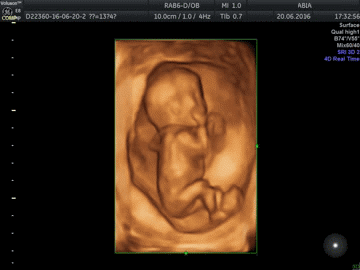

Также во время процедуры вы можете получить первое фото малыша и записать УЗИ на электронный носитель. Любой маме хочется как можно скорее увидеть своего кроху – клиника «АБИА» предоставляет такую возможность. После скрининга вам на память останутся фото и видео этого чудесного периода.

Важность первого УЗИ скрининга не нужно недооценивать, ведь он позволяет на ранних сроках оценить состояние здоровья плода и возможные риски патологий. Клиника «АБИА» предлагает широкий спектр услуг для будущих мам: от полного ведения беременности до отдельных процедур. У нас вы можете пройти ультразвуковое и биохимическое исследование на сроке 11-13 недель беременности. Современное оборудование клиники - экспертный аппарат Mindray Resona 6 позволяет с максимальной точностью определить, насколько здоровым родится малыш, какие возможные риски существуют. Вы получите рекомендации от опытного врача, которые помогут максимально сохранить здоровье крохи, а также – первые фото и видео с УЗИ. Ощутите радость материнства и начните заботиться о малыше ещё задолго до его рождения!

| Скрининговое УЗИ плода + 3D/4D УЗИ (один плод) | 5500 |